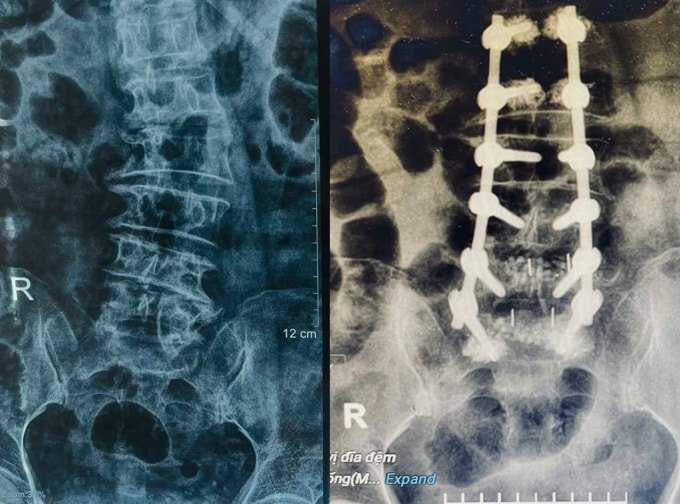

Trường hợp nặng, bác sĩ có thể đề nghị phẫu thuật để ổn định và làm thẳng cột sống, ví dụ cắt bỏ một phần xương, đĩa đệm hoặc hợp nhất các đốt sống, bơm xi măng... Người cao tuổi thường có các bệnh nền kèm theo nên trước khi phẫu thuật có thể cần làm các xét nghiệm, chụp chiếu đánh giá các chỉ số nội khoa và tình trạng sức khỏe tổng thể. Do đó, bác sĩ Thắng khuyên người cao tuổi nên đến khám và điều trị tại các cơ sở y tế đa khoa để chẩn đoán toàn diện và phối hợp các phương pháp điều trị hiệu quả.

Với sự hỗ trợ của máy móc hiện đại như dao cắt xương siêu âm, máy theo dõi chức năng tủy sống trong lúc mổ, hệ thống chụp X-quang liên tục C-Arm... các ca phẫu thuật diễn ra nhanh chóng và an toàn hơn, tránh được các tổn thương thần kinh, ngăn ngừa những biến chứng nguy hiểm. Thông thường, ngày đầu tiên sau mổ, người bệnh giảm đau đáng kể và có thể tập vật lý trị liệu.